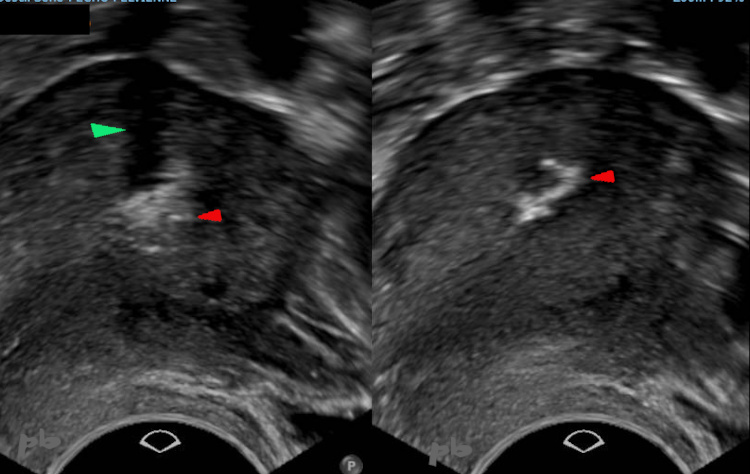

(même patiente que 21)

Révision utérine il y a 4 mois.

Echographie endovaginale.

Progression des calcifications (►) par rapport à l’échographie précédente 2 mois plus tôt.

Cône d’ombre (►)

Accouchement par voie basse il y a 2 mois et demi. Métrorragies.

Persistance d’un résidu placentaire (►) ponctué de petites calcifications.

Endomètre (★).

Placenta acreta. Résidus placentaires laissés en place lors de l’accouchement (★).

Evolution attendue vers la régression, la dévascularisation (absence de flux en doppler couleur), et la calcification (►).